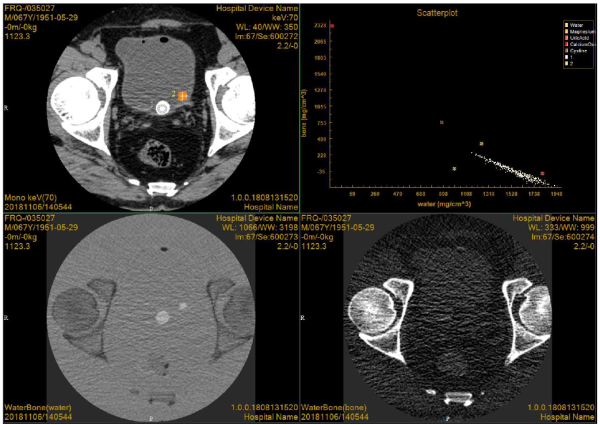

业内首创32层能谱技术推动高端能谱技术广泛普及

CT能谱成像是一种新兴技术,最早产生于20世纪70年代,但由于受到软硬件的限制而未能广泛应用。21世纪出现的以双kV为核心技术的能谱CT图像,为能谱成像的临床应用与研究创造了可能性。能谱CT是利用物质在不同X射线能量下产生的不同的吸收来提供比常规CT更多的影像信息的CT。与常规的单参数CT图像相比,能谱CT成像拥有涵盖多参数、定量分析的全新成像模式。

Precision 32精密断层能谱CT首次将目前高端CT具备的能谱成像技术广泛应用到32层CT,对常规CT难以定性的病灶和组织进行定性诊断和定量分析,提高诊断的精确度和安全性,将CT影像诊断成功率提升到一个全新的高度。